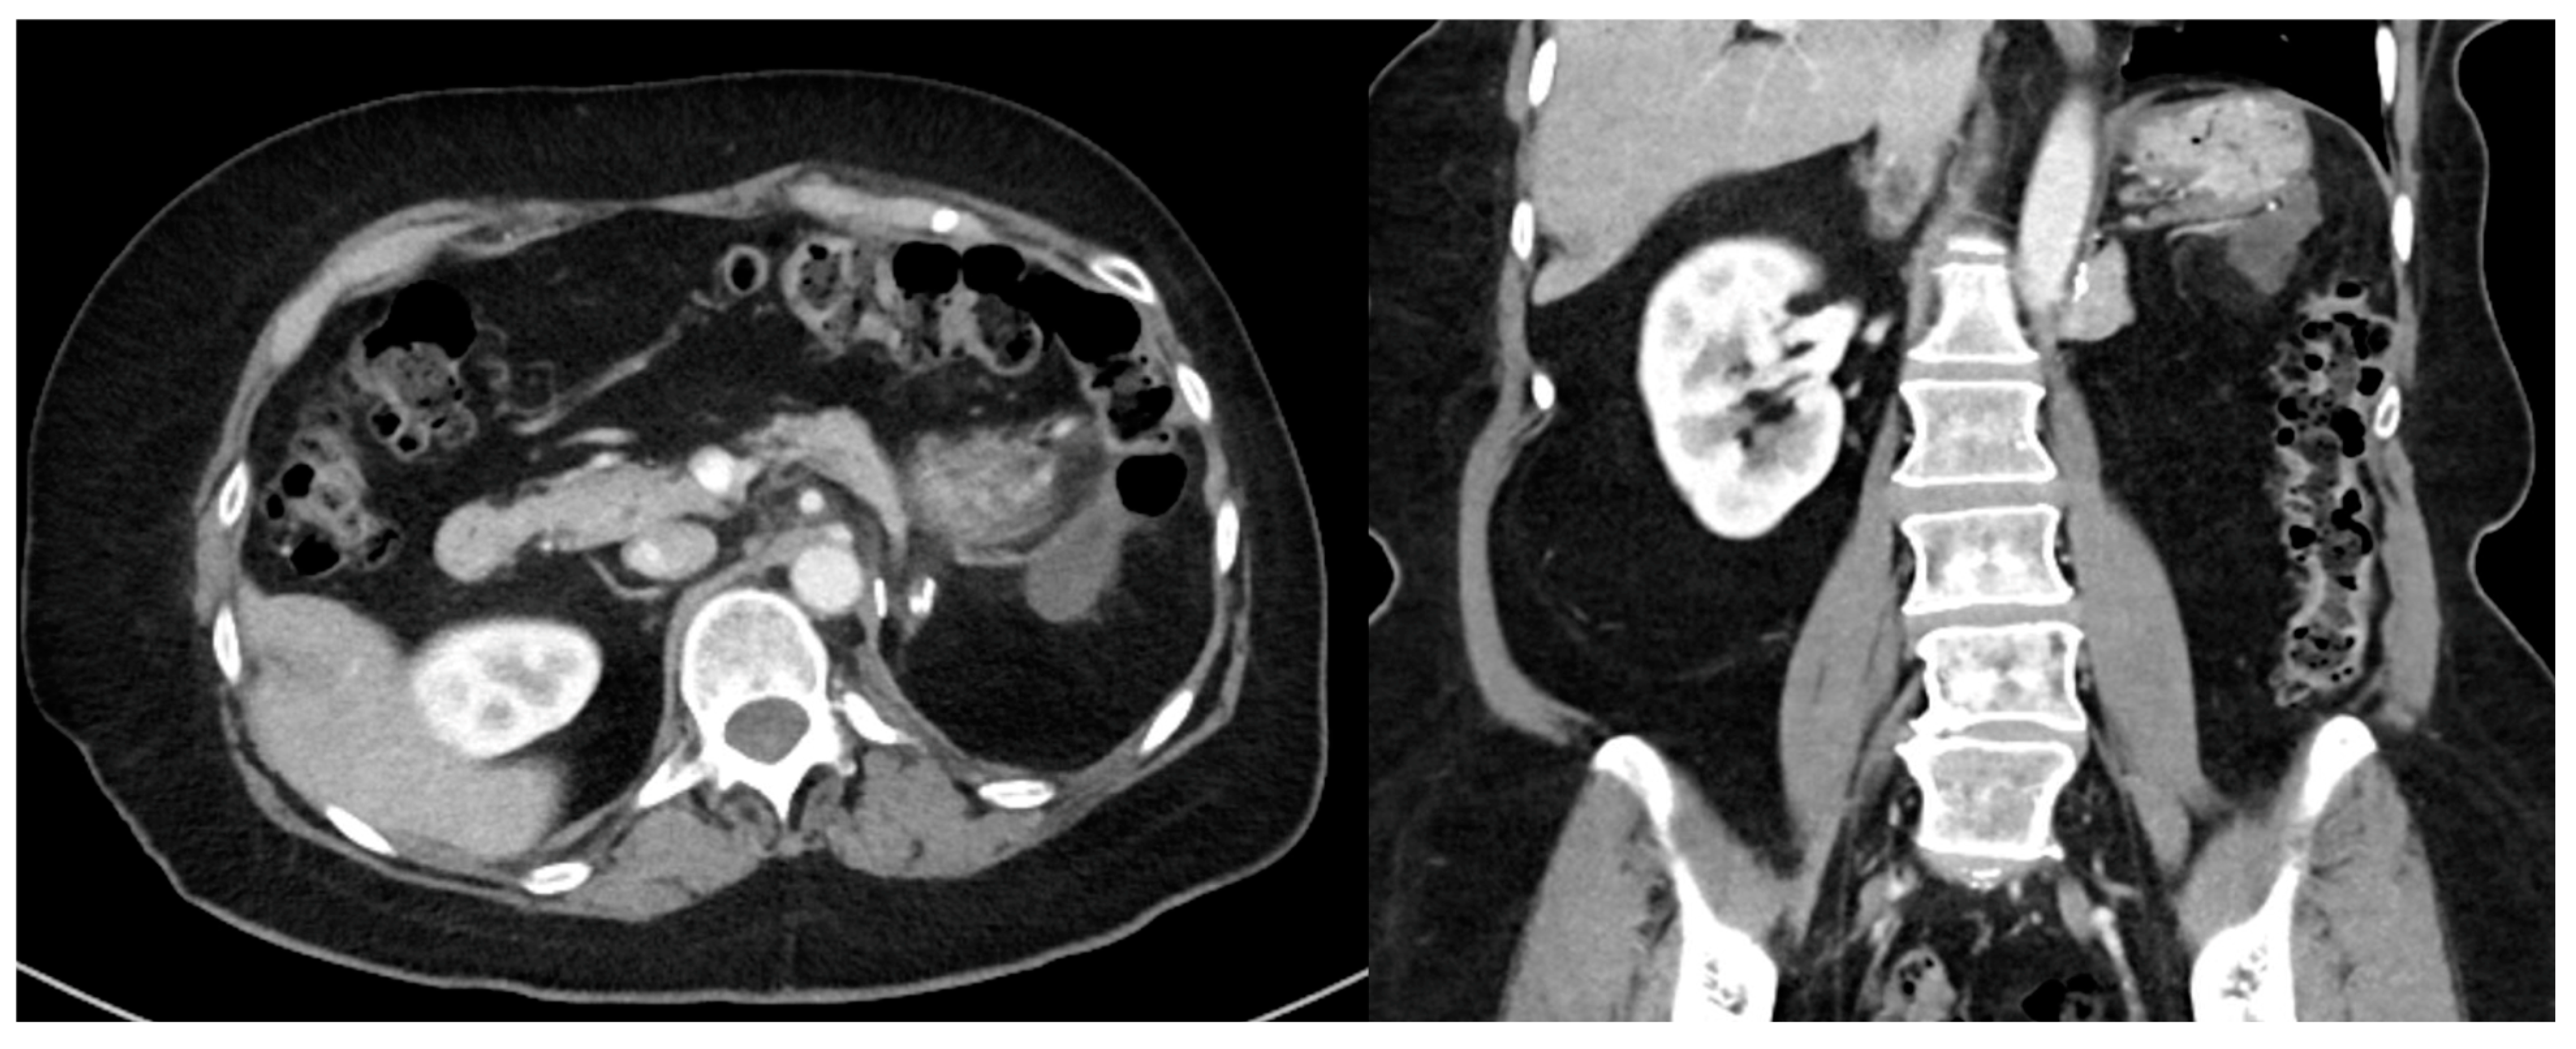

2. Imaging

- High-quality, contrast-enhanced CT imaging of the chest, abdomen, and pelvis should be performed when tumor recurrence is first identified.

- MRI may be useful to help delineate pelvic disease or extent of tumor involvement.